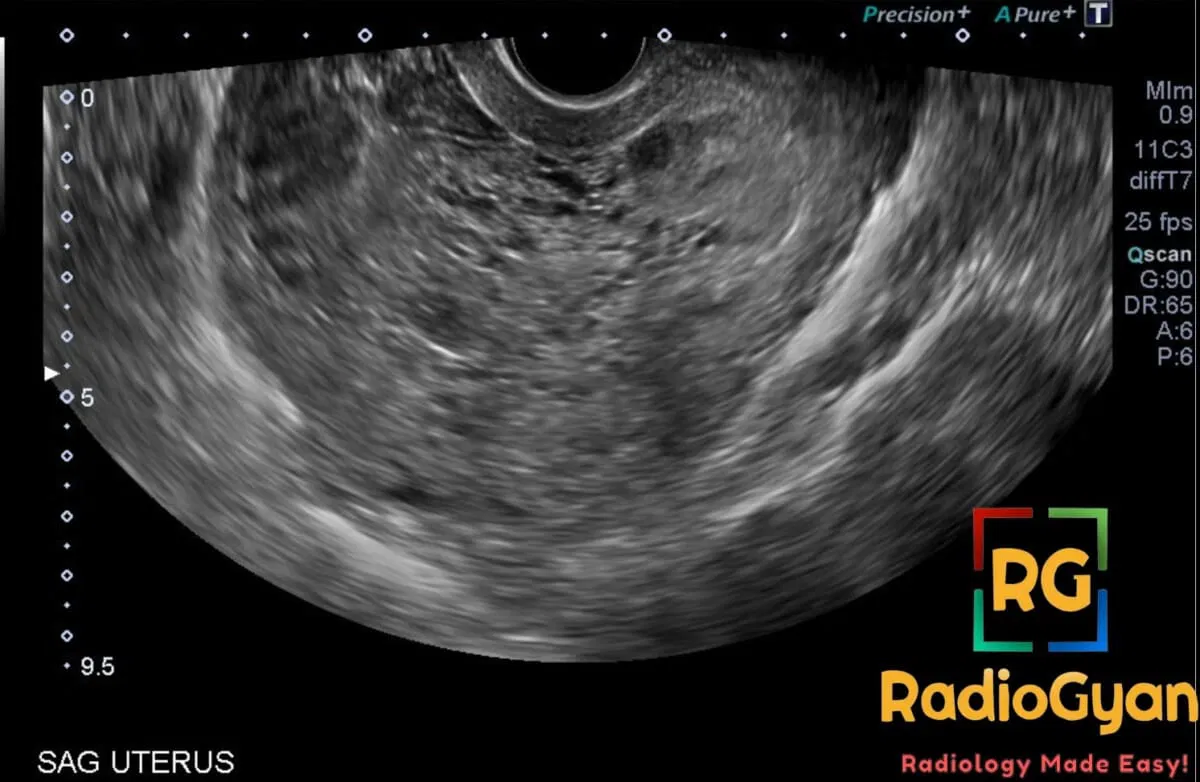

Hydatidiform mole (uterus)

The snowstorm appearance in the uterus on ultrasound classically reflects a hydatidiform mole. It shows a heterogeneous, echogenic intrauterine mass with innumerable tiny anechoic cystic spaces representing hydropic chorionic villi, typically without a normal fetus.

The echogenic mass with countless microcystic interfaces creates diffuse bright echoes resembling a snowstorm, often obscuring normal gestational structures.

Proliferation of trophoblasts and hydropic swelling of chorionic villi generate myriad fluidโtissue interfaces. The dense scatterers and internal hemorrhage produce the characteristic speckled echogenic pattern.